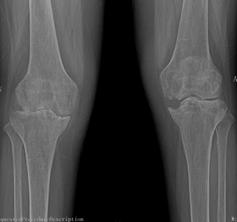

2015年10月,我院骨科二區(qū)迎來了62歲的李姓患者,她是一名類風(fēng)濕性關(guān)節(jié)炎的患者,病程10年。10年前,她被查出患有嚴(yán)重的類風(fēng)濕性關(guān)節(jié)炎,全身多處小關(guān)節(jié)疼痛,自那以后,患者就長期依靠激素來控制病情。2年前,患者雙側(cè)膝關(guān)節(jié)開始出現(xiàn)疼痛、腫脹,起初還能下地走200米左右,后來走50米都感覺費力,雙下肢膝關(guān)節(jié)出現(xiàn)變形,靠鎮(zhèn)痛藥物才能入睡。起初患者認(rèn)為,類風(fēng)濕關(guān)節(jié)炎是自己的老病,沒得治,拒絕來醫(yī)院就診。最后,實在痛苦難忍,遂在家人的陪伴下來到我院骨科二區(qū)就診。

來院后,骨科二區(qū)唐雄主任、廖浩主治醫(yī)師熱情接待了她。經(jīng)查,患者為嚴(yán)重的類風(fēng)濕性關(guān)節(jié)炎導(dǎo)致的雙膝關(guān)節(jié)破壞,雙膝關(guān)節(jié)內(nèi)翻畸形并嚴(yán)重的骨質(zhì)缺損,同時由于患者長期服用激素類藥物,其全身骨質(zhì)均有嚴(yán)重的骨質(zhì)疏松。患者得知病情嚴(yán)重性后,感到失望、沮喪,唐雄主任信心滿滿地安慰道,“您這種情況行膝關(guān)節(jié)置換術(shù),就能徹底解決關(guān)節(jié)疼痛和雙膝關(guān)節(jié)不能活動的問題?!庇谑?,病人又重新燃起了對生活的希望,并要求盡快進(jìn)行手術(shù)治療。